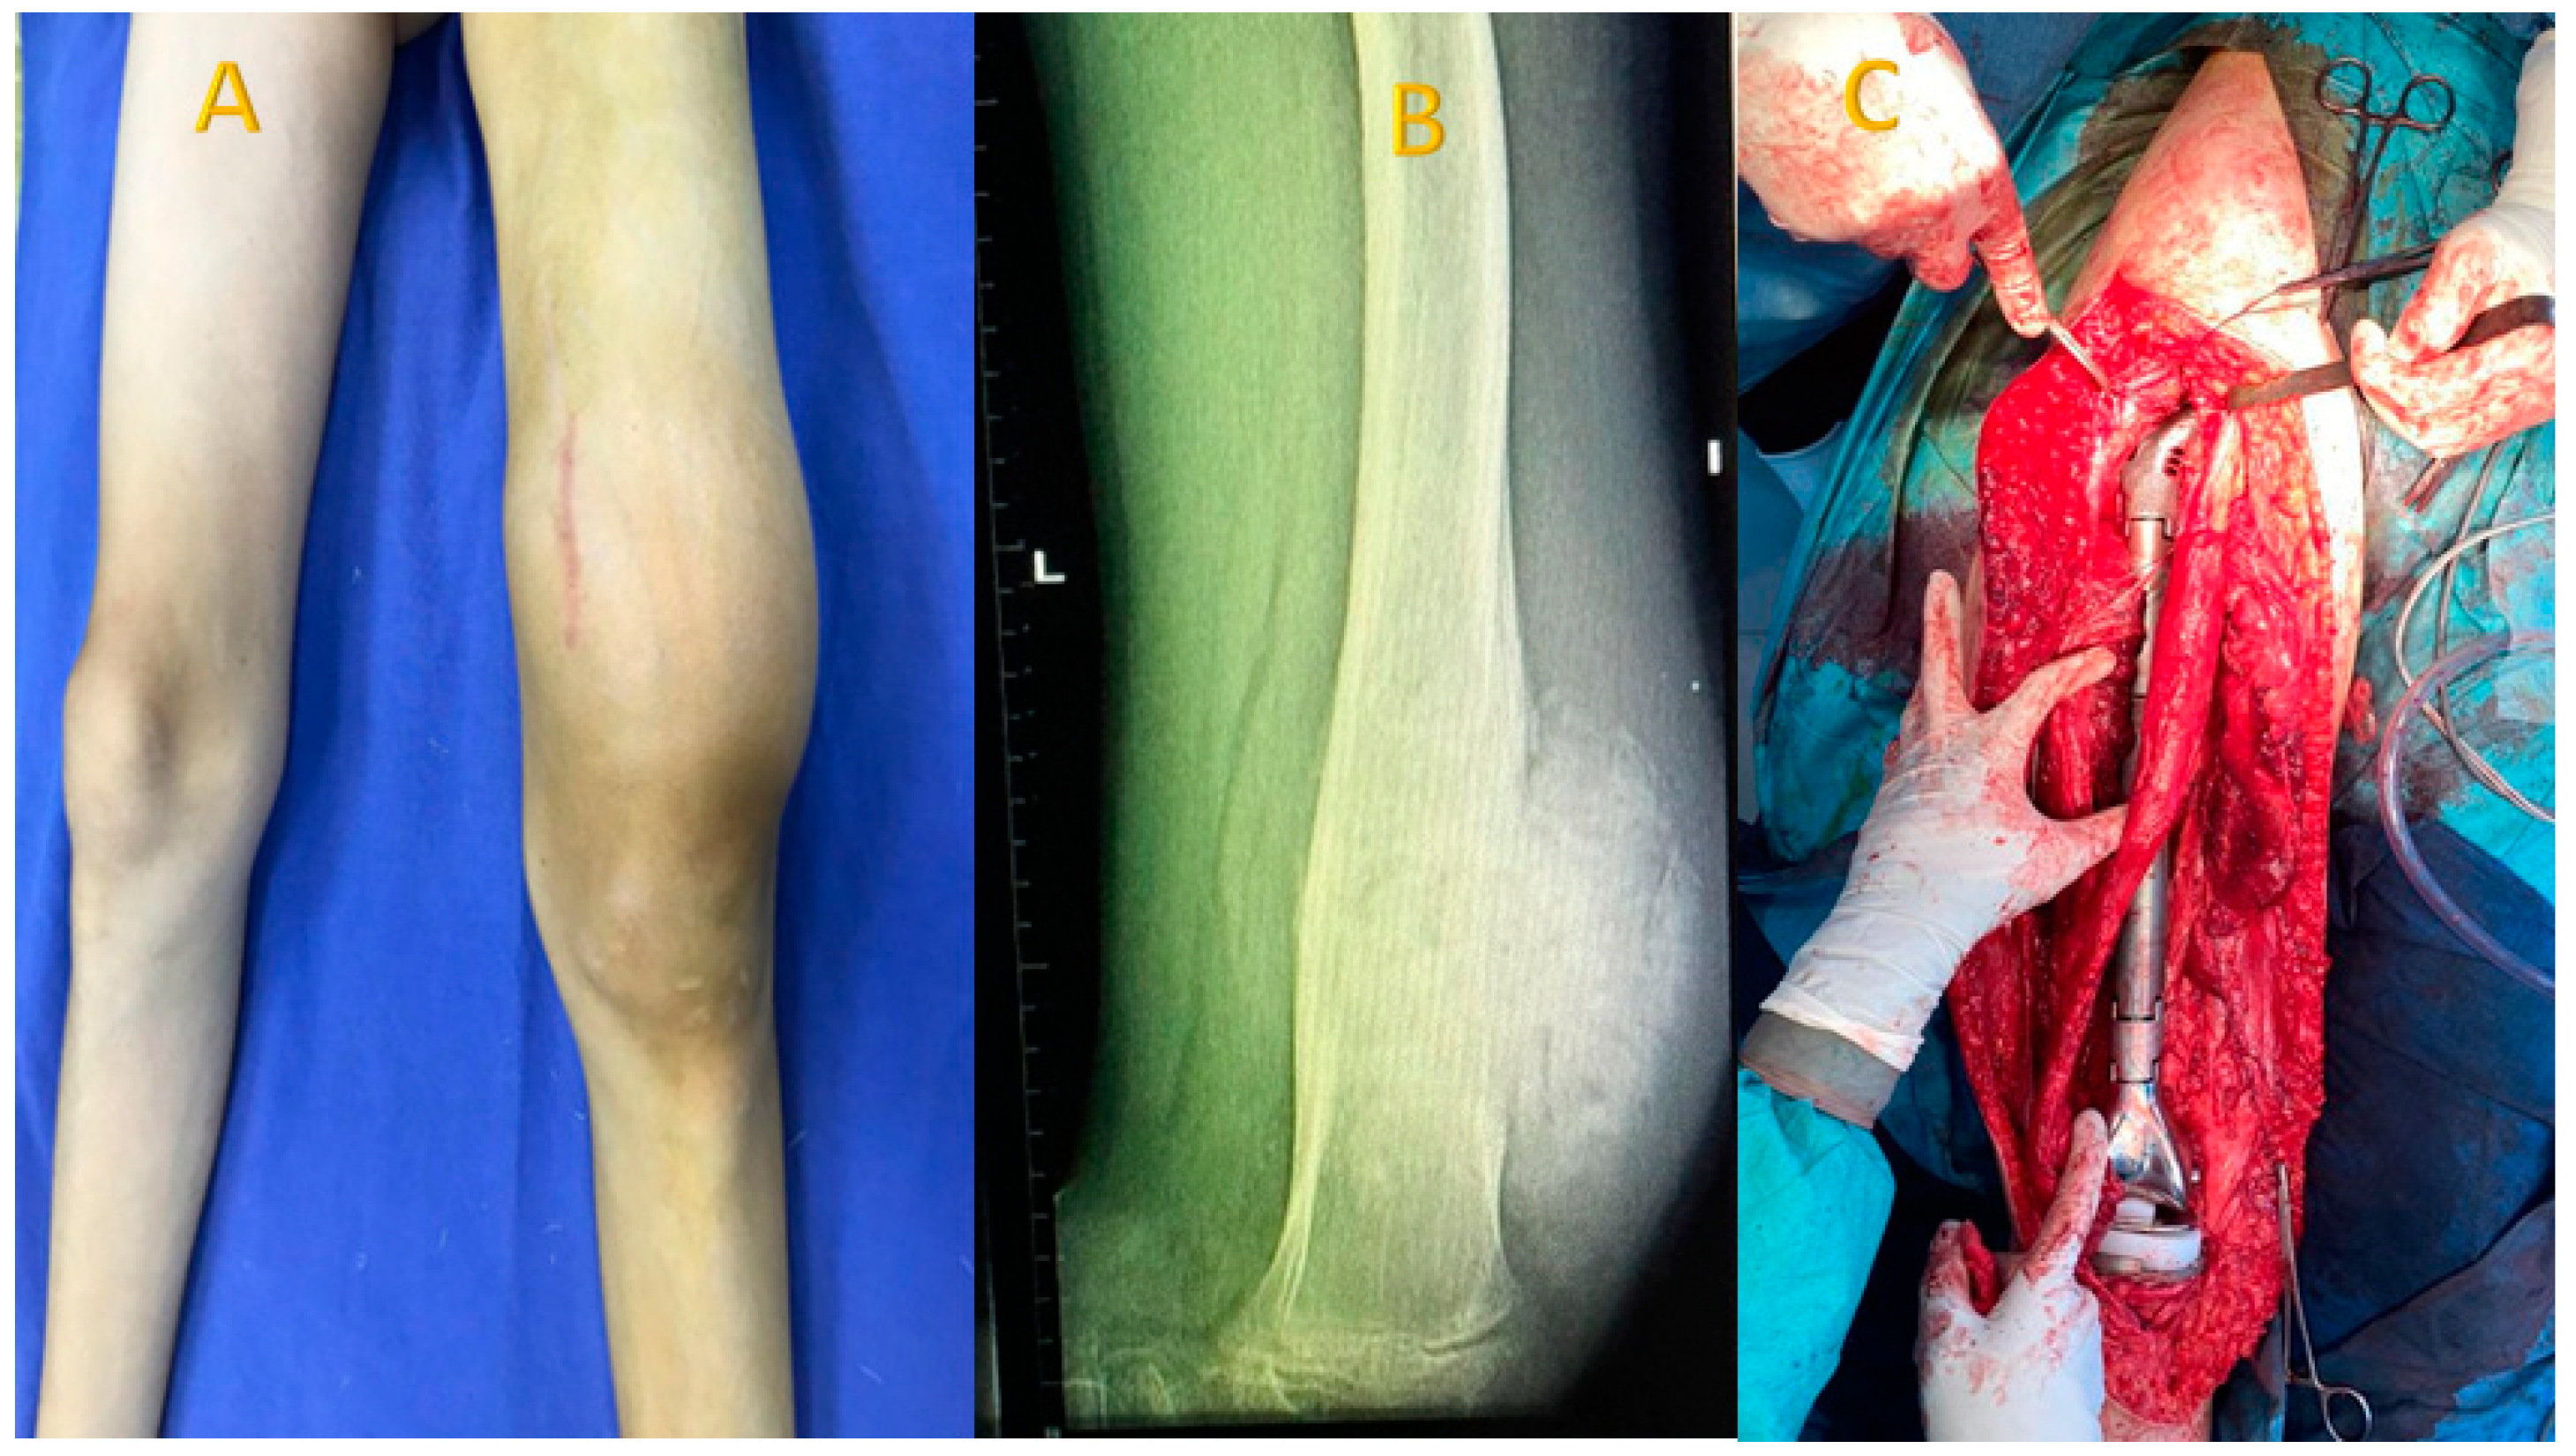

For the studied group, the main symptoms at presentation were attributed by the patient and relatives to trauma. The main symptoms were pain (93.8%), functional impotence (87.7%) and swelling (100%). Figure 2, Figure 3 and Figure 4 present the clinical, imaging and intra-operative appearance of the humeral and femoral OS for two of our patients.

Figure 4. Femoral OS in a 14-year-old male patient, 13 cm diameter tumour; (A) clinical aspect showing distal femoral tumour, with a central scar—the site of the biopsy; (B) femoral X-ray showing periosteal destruction and infiltration in adjacent tissues; (C) intraoperative aspect after removal of the tumour, the femur, and implantation of the articulated femur prosthesis.